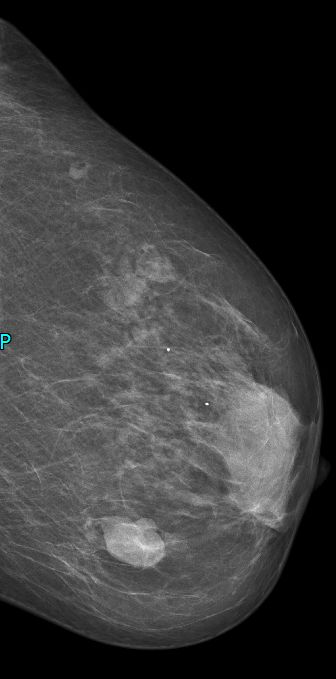

| intrazystisches DCIS | Eine 73-jährige Frau bemerkte in der linken Brust oben innen einen 3cm großen zystischen Tastbefund. Die Mammographie spricht für eine gutartige Zyste. Allerdings ist die Neubildung einer Zyste in dem Alter ungewöhnlich. | ||

![]() |